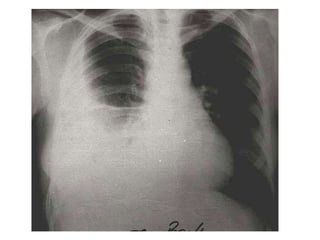

Condensación basal izquierda retrocardíaca

NEUMONIA ATIPICA (legionella)